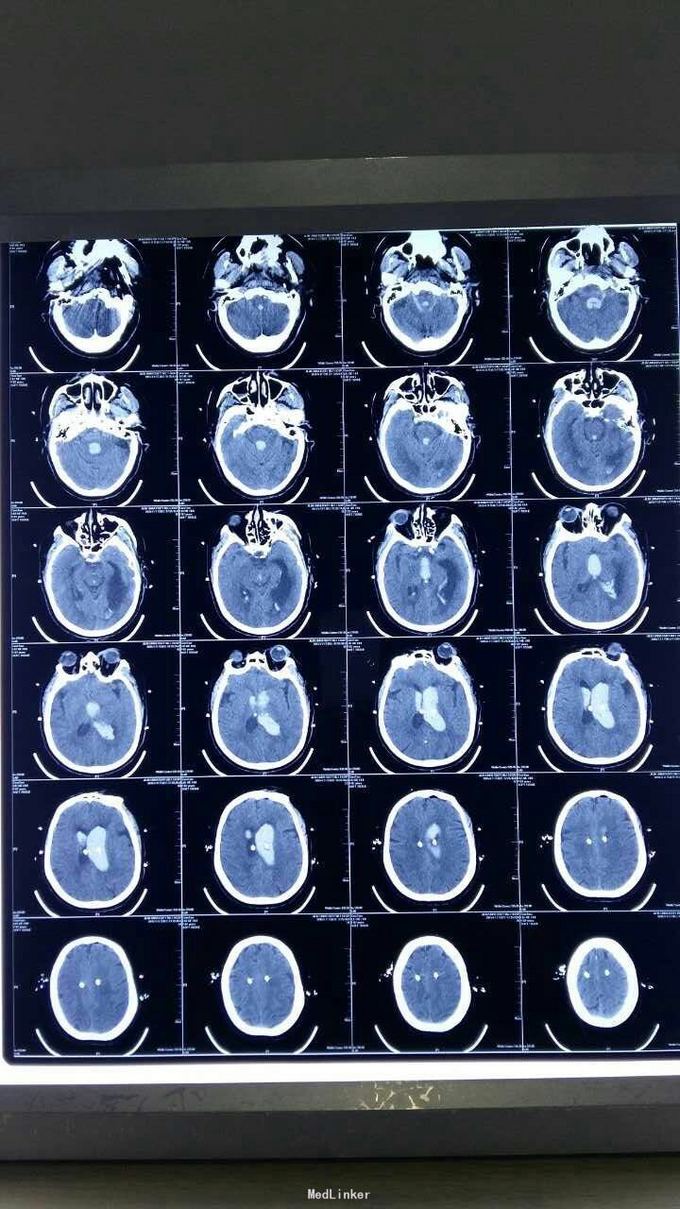

脑室外引流

突发意识不清2小时

脑室出血(全脑室铸形)行双侧脑室外钻孔引流十腰大池引流